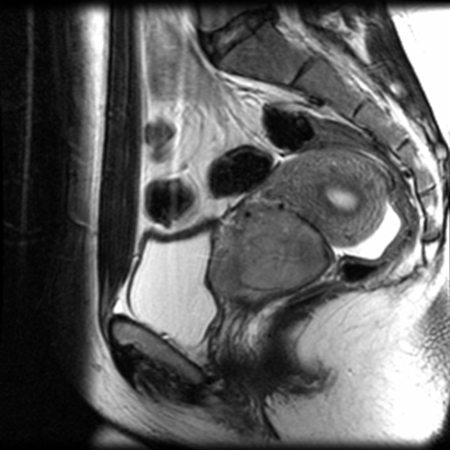

Cervical cancer

MRI for treatment planning

From the collection of Neil S. Horowitz, MD; used with permission